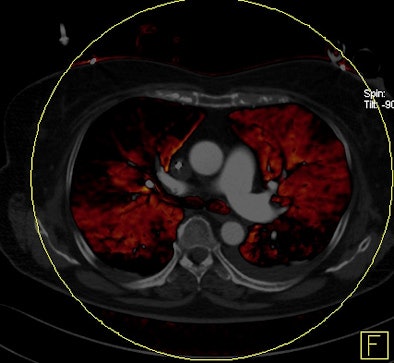

Dual-energy CT enables the selective display of iodine distribution within the pulmonary parenchyma following contrast-enhanced pulmonary CT angiography, which in turn permits the calculation of perfusion defect (PD) size in patients with suspected PE.

Depending on the shape and pattern of the defects at dual-energy CT, perfusion defects due to PE can generally be distinguished from, for example, patchy defects signaling other pathologies of the lung parenchyma, Bauer said.

The researchers measured perfusion defect size in the lung parenchyma caused by PE on dual-energy iodine distribution maps, and expressed it in two ways: as absolute quantification (VolPD in mL) and relative to the total lung volume (RelPD in %).

"When we did lung perfusion, the analysis was restricted to the field-of-view," which is limited due to the smaller second detector on the dual-source CT scanner, he said. As a result "there were 40 patients with no coverage loss, eight patients with up to 5% coverage loss, and five patients with up to about 10% of coverage loss in the peripheral" areas of lung parenchyma, he said.

| Patient with bilateral segmental and subsegmental PE and large perfusion defects on dual-energy iodine distribution maps. All images courtesy of Dr. Ralf Bauer. |